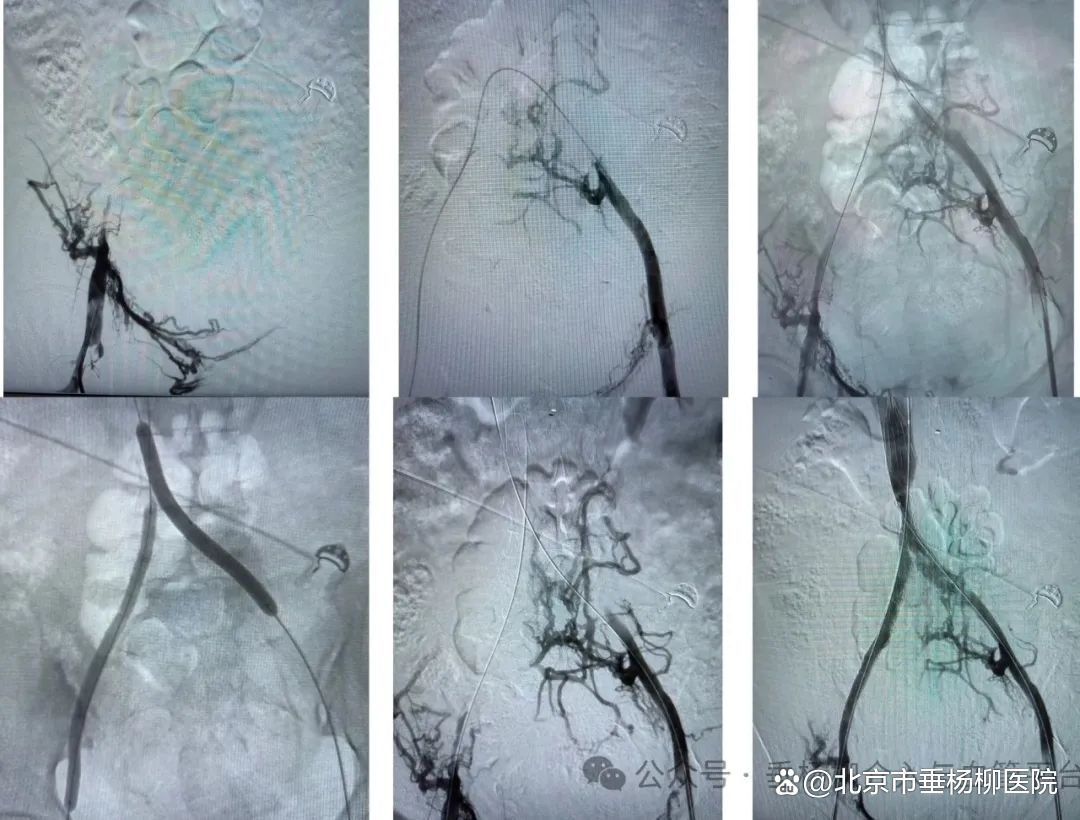

抱着最后一线希望,经中科院肿瘤医院推荐,家属带李女士来到清华大学附属垂杨柳医院介入与血管外科找到了杨永久医生。面对患者无法平卧的难题,杨永久团队联合麻醉科创新制定“坐位插管全麻转平卧”方案。在多学科高效协作下,仅用一天半完成术前评估,次日即实施介入手术。术中造影显示患者双髂静脉至下腔静脉远端完全闭塞,杨永久带领介入与血管外科医师白玉锁,凭借娴熟技术,一小时内成功开通闭塞段,完成球囊扩张并精准植入支架。当造影剂如溪流般在血管中顺畅流淌时,手术室内响起如释重负的掌声。